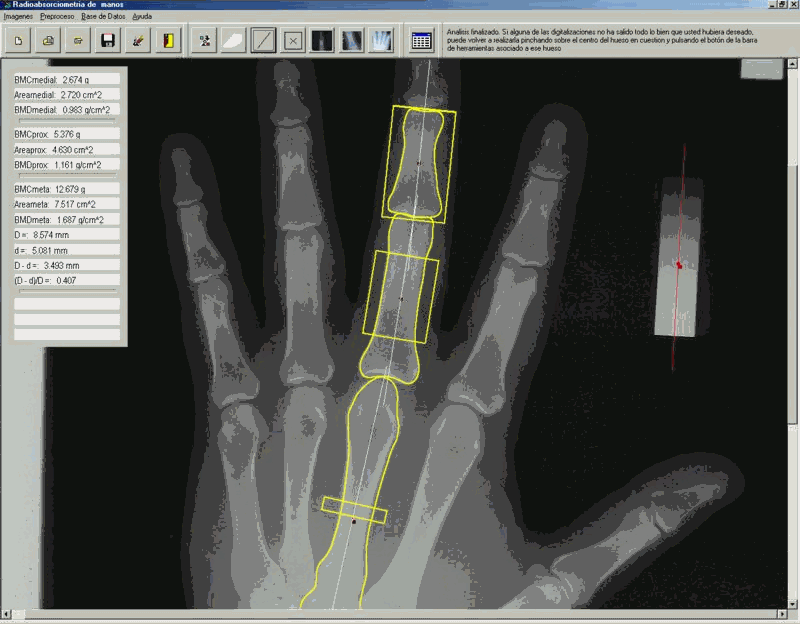

El programa de análisis de imagen se ha desarrollado de novo bajo el entorno de Borland Delphi 5. El primer paso consiste en la determinación de la curva de calibración basada en el perfil longitudinal de la cuña de aluminio. A continuación, un módulo de segmentación determina la región de interés (ROI) basandose en la metodología de snakes o ASM que se comenta más adelante. Posteriormente, se determina el área de la superficie segmentada y la suma de valores de densidad óptica en dicha área (Figura 1). La densidad mineral ósea (DMO) resulta del cociente entre suma total de densidad en la ROI divido por el área en píxels y se expresa en unidades arbitrarias (AU).

Los resultados del análisis se muestran de modo inmediato en pantalla (fig.2) y posteriormente son guardados en una base de datos relacional desarrollada al efecto. El software permite imprimir un informe completo de los datos densitométricos determinados por RXA así como informes acumulativos con información clínica y de otros tipos de densitometría, que pueden incluirse en la misma base de datos de forma independiente. Estos informes son remitidos al médico a cargo del paciente para su valoración, con una interpretación orientativa de los resultados obtenidos.

Figura 2. Segmentación de falange medial, proximal y metacarpiano, con detalle de las regiones de interés (ROI). En pantalla se muestran los cálculos realizados de Area, CMO y DMO.